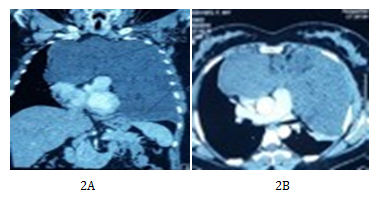

A woman aged 48, with no notable medical history was referred to our medical service for atypical chest pain and experiencing dyspnea, Sadoul stage II, for 3 months. The clinical examination revealed a patient in good condition with a left pulmonary consolidation on chest x-ray (CXR). The dermatological examination was unremarkable. Chest radiography showed an opacity occupying the lower half of the left hemi thorax extending to right para-cardiac area (Figure 1). Chest CT (Figures 2A & 2B) showed an anterior mediastinalmass with a heterogeneous tissue density image with an exothoracic component, without signs of parietal invasion. This mass was compressing the heart chambers and supra-cardiac vessels without invasion. Laboratory tests included the assay of alpha-fetoprotein and beta HCG and were both negative. An earlier mediastinotomy exploration was performed. The exploration revealed an encapsulated tumor/tissue component with gelatinous appearance that suggested a huge bronchogenic cyst. The indication for surgical resection had been opted without carrying out a prior biopsy. Thoracotomy through the anterolateral left 4th intercostal space was performed. The exploration revealed an encapsulated anterior mediastinal tumor with an exothoracic component creeping into the 2nd left intercostal space without parietal or mediastinal invasion. Complete tumor resection including the exothoracic component was performed. Pathological examination (Figures 3–5) of the tumor tissue undertaken by two different laboratories confirmed the diagnosis of benign myxoid mediastinal neurofibroma. The postoperative course was uneventful, the patient was discharged post-operatively on day 5.

Figure 2 Anterior mediastinal mass with heterogeneous tissue density image with exothoracic component without signs of parietal invasion. This mass is compressing the heart chambers and repressed supra-cardiac vessels without invasion.

Myxoid neurofibroma is a rare tumor. It usually occurs on the face, shoulders, arms, around the nails and feet.2 Unlike these locations most of which are asymptomatic,2,3 the mediastinal location is of particular importance because of its proximity to the mediastinal organs. The symptomatology is dominated by chest pain, cough, dyspnea, dysphagia or superior vena cava syndrome. The CT scan features are that of a mediastinal mass compressing or displacing structures without invasion. In our patient it revealed a large heterogeneous mass of tissue with cystic components occupying the anterior mediastinum with enhancement after contrast injection and compressing the mediastinum and both lungs without signs of invasion. To our knowledge this is the first case of mediastinal location of a myxoid neurofibroma. It poses a problem of differential diagnosis with anterior mediastinal masses including thymic epithelial tumors and lymphomas. Thus, certainty of the diagnosis is based on histology. This diagnosis is a challenge to the pathologist for two reasons. Firstly, because of many diagnostic possibilities (egg. an aggressive angiomyxoma, fibromyxoidsarcoma, low-grade myxoidliposarcoma etc.).4 Secondly, biopsy fragments that are small do not allow a full pathological and immunohistochemical study.5 Hence it is now important to include myxoid neurofibroma in the differential diagnosis and to make earlier mediastinotomy biopsies for confirmation of the proper diagnosis. In the case of our patient, the first exploration before completion of the biopsy revealed a resectable encapsulated mobile anterior mediastinal tumor, resulting in a complete tumor resection without any biopsy. Indeed, this resection remains the only therapeutic approach in myxoid neurofibroma. One must take out the tumor in its entirety to prevent recurrence.1 This must be performed in view of clinical signs of mediastinal compression and should be considered as early as possible to avoid the occurrence of superior vena cava syndrome with thromboembolic complications. The choice of surgical approach will depend primarily on the location of the tumor. In our patient, it was a left anterolateral thoracotomy. It allowed complete resection of the tumor despite its extension in the right hemi-thorax. A clamshell approach could also be carried out but it was deemed unsuitable in this case. Although myxoid neurofibroma is a rare disease and unusual in the chest, mediastinal location must be thought of and now considered and included in the differential diagnosis of mediastinal masses. Its management is surgical and based on total resection as the only guarantee of a good prognosis.